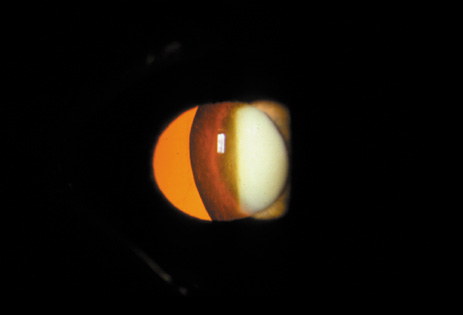

POSTERIOR SUBCAPSULAR CATARACT

The PSC is the least prevalent subtype in most population-based studies.18 These cataracts often occur in combination with nuclear or cortical cataracts in the later stages. They are easily noticed on retroillumination because they are usually located centrally, and may interfere with funduscopy (Fig. 12). In early stages, patients usually complain of subjective symptoms such as glare disability32 and difficulty focusing on near objects. This is because when the pupil constricts during accommodation, the light entering the eye becomes concentrated centrally, where the PSC is also located. This causes light scattering and interferes with the ability of the eye to focus an image on the macula. In addition, these opacities lie at or near the nodal point of the eye, further interfering with focusing of the image on the macula.

One can examine this type of cataract with direct illumination, using the narrow and broad beams of the slit-lamp to show the characteristic granular inner surface immediately in front of the posterior capsule (Fig. 13). The problem with this technique, however, is that patients may not tolerate any prolonged direct illumination because of the glare. Retroillumination is therefore more useful for revealing the outline of the opacity, since it is usually seen as an “island” in the center of the posterior capsule, which is further highlighted by the shadow cast by the opacities.33 However, in the early stages of this type of cataract, the dust-like particles that might be noticeable in the central posterior subcapsular area with direct illumination disappear or are difficult to see with retroillumination (Fig. 14). Eventually this “dusting” becomes dense enough to cast a shadow and thus appear on retroillumination. The smooth orange background of the fundus helps to highlight the rough, irregular pseudopodia-like edges of the central opacity. In advanced stages, the PSC may become a thick, calcified plaque (Fig. 15). During surgery, excessively vigorous scraping or vacuuming of the calcified opacity can lead to rupture of the posterior capsule. Usually, small remnants that are left behind after surgery are reabsorbed and do not interfere with vision; otherwise, they are easily treated with a neodymium : yttrium (Nd:YAG) aluminum garnet laser. Pathologic evidence suggests that most PSCs result from the migration of bow region cells into the potential space (along with accumulated cellular debris) between the posterior capsule and the cortex.34–36

Fig. 14. A PSC, showing vacuoles and dust-like material in the potential space between the posterior cortex and the capsule.